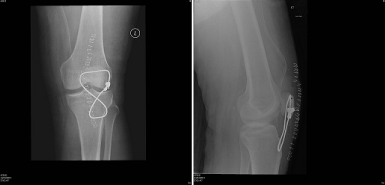

A 53 year-old male presented with history of fall down over his flexed knees while descending from stairs and complaining of bilateral knee pain, swelling and inability to bear weight. He is known to have chronic renal failure secondary to membranous glomerulonephritis for the last 15 years. He is on hemodialysis three times per week since that time. He has history of two rejected renal transplant in the last seven years. Clinical examination revealed bilateral severe effusion around the knee with tenderness to palpation. A palpable left infrapatellar and right suprapatellar gaps are detected. His knees were in 20-30 degrees of flexion with restricted active flexion due to pain and effusion. He has bilateral loss of extensor mechanism. Bilateral knee x-rays showed left knee patella alta with Insall-Salvati ratio of 0.48. Right knee x-ray showed no obvious abnormality with Insall-Salvati ratio of 1.07 (Figure 1–3).

Figure 1 Bilateral knee AP radiograph at the time of injury.